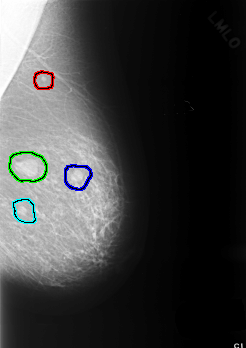

C_0364_1.LEFT_MLO

FILE: C_0364_1.LEFT_MLO.OVERLAY

TOTAL_ABNORMALITIES 4

ABNORMALITY 1

LESION_TYPE MASS SHAPE ROUND MARGINS CIRCUMSCRIBED

ASSESSMENT 2

SUBTLETY 5

PATHOLOGY BENIGN

TOTAL_OUTLINES 1

BOUNDARY

ABNORMALITY 2

LESION_TYPE MASS SHAPE OVAL MARGINS CIRCUMSCRIBED

ASSESSMENT 3

ABNORMALITY 3

LESION_TYPE MASS SHAPE LOBULATED MARGINS CIRCUMSCRIBED

ABNORMALITY 4